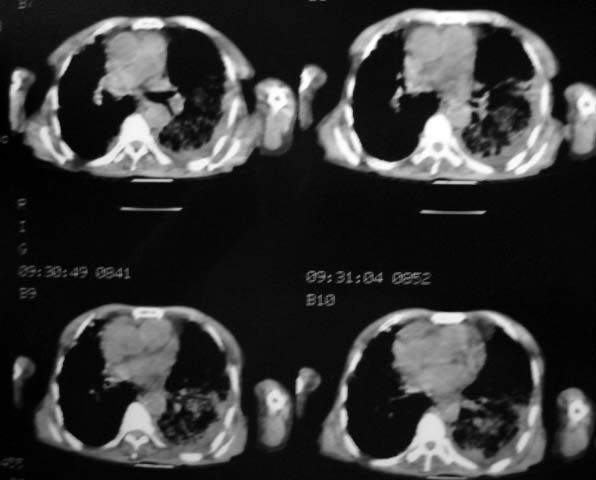

男,85岁,发热2月, 血常规:hgb99g/l.rbc2.55×1012/l.wbc3.8×109/l.n78.2%  l20.7% m1.1%.  hct26.3% .血沉20mm/hg.痰检结核杆菌阴性。ddp阳性。痰少粘稠色白。无咳血。

1.右上肺陈旧性肺结核灶;

2.左上肺、双下肺及右中叶肺炎(左上肺肺炎治疗后好转)

右上肺陈旧性肺结核灶,双肺感染灶〔大部份纤维化〕,肺气肿.

双肺继发型肺结核,肺纤维化,肺气肿,胸膜肥厚黏连。